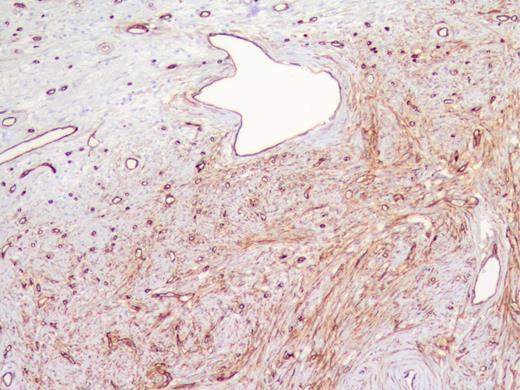

The specimen was a 3.5 ×3 ×3-cm white, firm, well-circumscribed mass located in the head of the pancreas (Fig. 3). The mass was found to be compressing the distal aspect of the main pancreatic duct. All 15 lymph nodes received in the specimen were negative. Histologically, the tumor is well circumscribed from normal pancreatic tissue and composed of spindle cells that in some areas form short ill-defined fascicles and in other areas are randomly arranged in a dense fibrohyaline stroma. A well-developed vascular network was visualized throughout the tumor with vessels of a stag horn appearance with thin hyaline wall and tumor growth around (Figs 4 and 5). No significant mitotic activity or tumor necrosis was noted. Immunostaining was positive for CD34 (Fig. 6) and BLC-2; focally for B-catenin, and focally weak staining for CD99, compatible with fibroblastic origin. The tumor cells were negative for the following cell markers: CD117, CAM5.2, AE1/AE3, EMA, synaptophysin, chromogranin, CD56, PR, SMA, Desmin, S100, MelanA and HMB45. The M1B1 proliferation index was low (<5%). These findings in combination are consistent with a SFT.

High power showing spindle cells of minimal nuclear pleomorphisms.